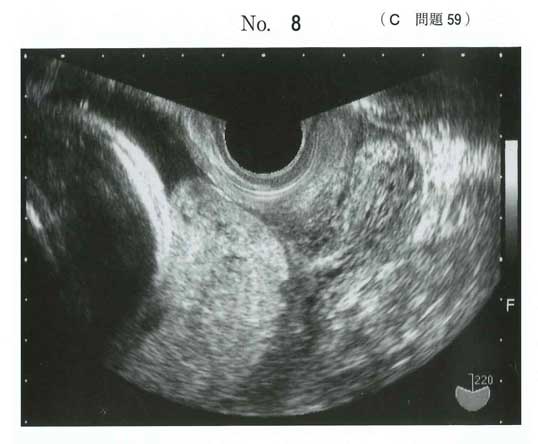

117C-59117C-59

a 帝王切開を行う

112B30と画像まったく一緒では?